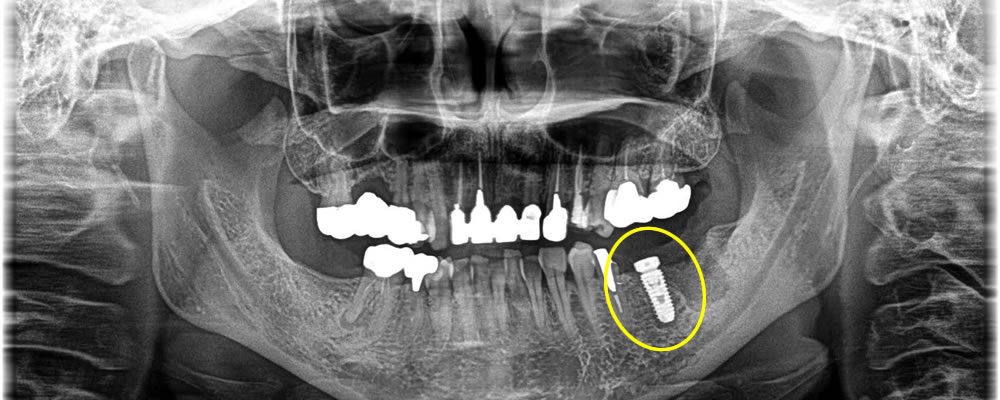

インプラント治療完了後のレントゲン・口腔内写真

4ヵ月待機期間を設け、しっかりと骨と結合している事を確認した後に型取りを行いました。その後、完成した上部のジルコニアの人工歯を装着して治療完了です。審美面・咬合も回復し、患者さまに満足していただく事ができました。